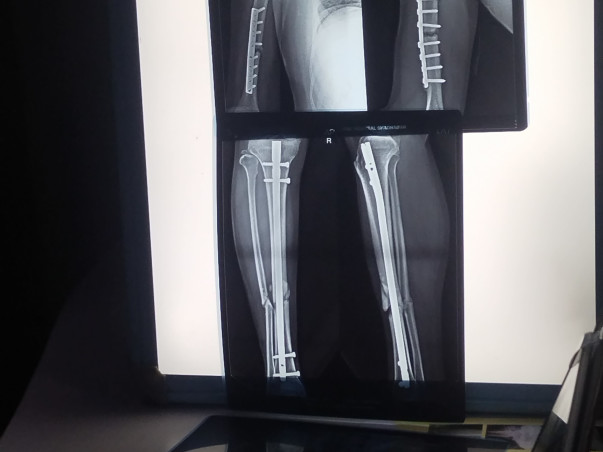

However, srinivas is now facing a significant challenge in his own life. He has been diagnosed with an accident followed by right hand spine and right leg damage and his treatment requires immediate and substantial medical intervention. The cost of treatment is overwhelming, and despite his immense contributions to society, he finds himself in need of help at this critical juncture.

I met with a road accident and have been suffering from a severe spine and leg injury for the past few months. The doctors have advised me to undergo spine and leg surgery, but I have been confined to bed rest since the accident. I am receiving medication at Lotus Hospital in Shadnagar, Telangana, but I have not yet been admitted due to a lack of funds.